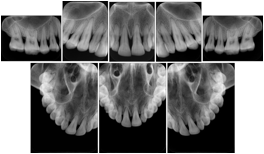

2. A patient requests cosmetic surgery to enhance their facial appearance. The case requires consultation between an orthodontist in New York and an oral surgeon in California. The cephalometric series of 2D projections constructed from the volumetric CT data that is used for the discussion is arranged by a Structured Display for transfer between the two practitioners.

Cephalometric Series Structured Display

Figure OO-2. Cephalometric Series Structured Display